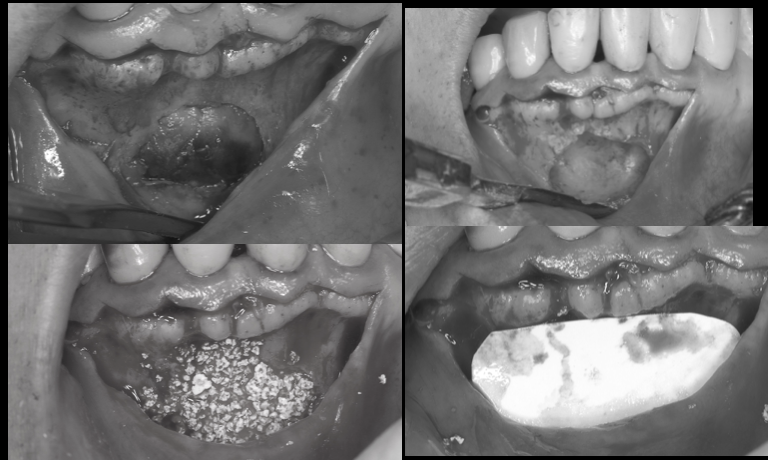

[池袋 歯医者]歯の移植〜インプラントをする前に...